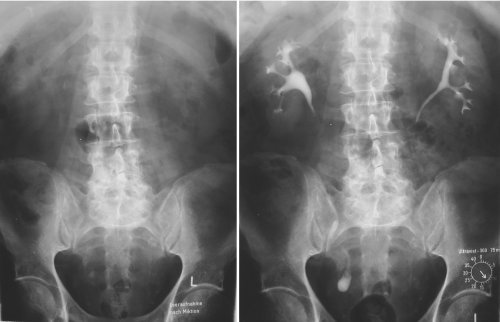

Röntgen

Röntgenuntersuchungen sind wichtiger und notwendiger Bestandteil urologischer Diagnostik. Trotz der Zunahme der sonographischen Untersuchungsmöglichkeiten (Ultraschall, Doppler) ist die Röntgendiagnostik bei bestimmten Fragestellungen weiterhin unumgänglich.

Durch Kontrastmittel werden die Harnwege im Bild darstellbar und der Beurteilung zugänglich.

Urogramm